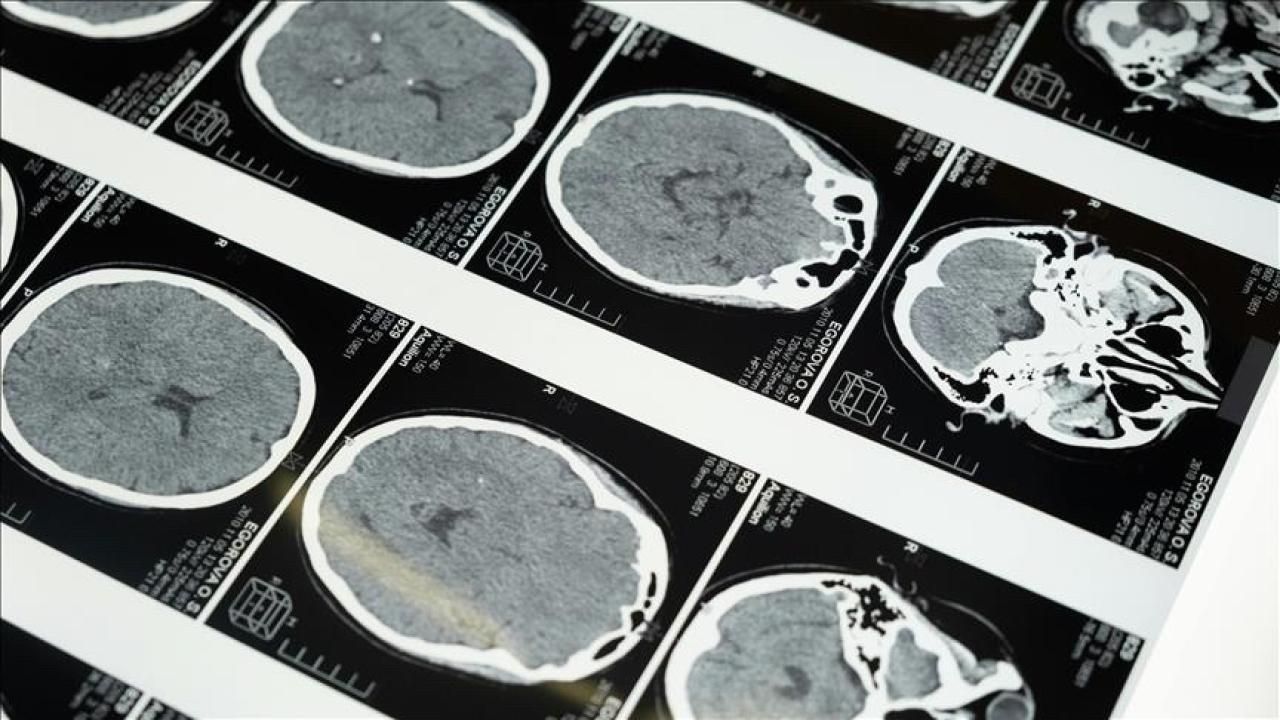

İstanbul'da düzenlenen 1. Dünya Girişimsel Nöroloji ve Nöroşirurji Kongresi'nin (WINNC 2025) organizasyon komitesinde yer alan, Eskişehir Osmangazi Üniversitesi Tıp Fakültesi Nöroloji Anabilim Dalı Öğretim Üyesi ve İnme Merkezi Başkanı Prof. Atilla Özcan Özdemir, felçin iki türü olduğunu söyledi: beyin damarlarının tıkanması (iskemik) ve beyin kanaması.

“Özellikle pıhtı nedeniyle tıkanan beyin damarını açma konusunda stratejiler geliştirildi. İnmenin erken evrelerinde yapılan damar açma tedavileri konusunda ülke olarak iyi bir durumdayız. İnme tedavisinde pıhtı nedeniyle tıkanan beyin damarını anjiyografi ile açmak mümkün. Bu sayede hasta 3 ay veya 1 yıl sonra işini yapabilir hale getirilebiliyor. İnme merkezlerinde yapılabilen bu işlemi, Bazı hasta grupları ilk 24 saat içinde İlk 24 saat çok kritik, bu “Ameliyatlar ancak felç merkezlerinde yapılabilir”.